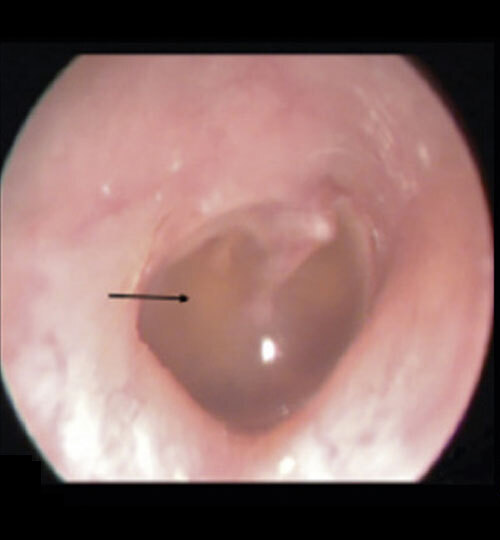

L’examen otoscopique (figure) met en évidence un épanchement plus ou moins abondant rétrotympanique responsable d’un aspect de rétraction de la membrane tympanique (de couleur variable : jaunâtre, parfois blanchâtre, parfois bleue) avec ou sans bulles, ou au contraire d’un bombement, traduisant un épanchement rétrotympanique aux mêmes caractéristiques avec une saillie des reliefs du marteau.

Le diagnostic différentiel otoscopique entre OMA et OSM n’est pas toujours aisé car il peut y avoir un épanchement dans les 2 cas ; c’est son aspect et l’association à une symptomatologie aiguë (otalgie ou fièvre) qui orientent le diagnostic. Cependant, des OMA récurrentes peuvent se chevaucher avec une OSM rendant le diagnostic plus difficile, notamment si une OSM est diagnostiquée quelques semaines après le dernier épisode d’une OMA récurrente.